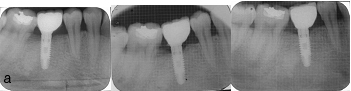

IOPA Immediately after Crown cementation, 1st and 3rd month follow up

IOPA Immediately after Crown cementation